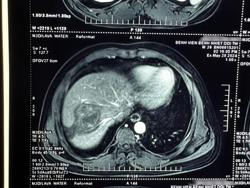

Thông tin từ Bệnh viện Bệnh Nhiệt đới trung ương cho biết, mới tiếp nhận bệnh nhân có ổ sán lá gan lớn vì sở thích ăn rau sống, đặc biệt là rau muống.

Nghiện ăn rau sống, đặc biệt là rau muống, rau ngổ trồng dưới ao, hồ, người đàn ông ở Phú Yên phát hiện ổ sán lá gan lớn trong bụng

Trong vòng 3 tháng đầu năm 2023, Bệnh viện Bệnh nhiệt đới TP HCM đã tiếp nhận điều trị 172 ca bệnh áp xe gan do sán lá gan lớn, toàn bộ bệnh nhân đều có thói quen ăn rau sống.